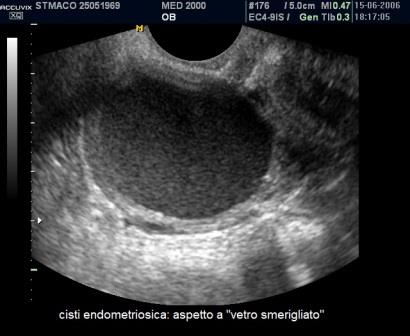

E' la localizzazione più frequente della patologia endometriosica rappresentando circa il 65% dei casi; gli aspetti ecografici più comuni delle cisti endometriosiche ovariche o endometriomi sono:

- contenuto "ground glass" ("a vetro smerigliato") legato all'accumulo di cellule ematiche che sfaldano dalla parete e di emosiderina;

La diagnosi differenziale deve essere posta nei confronti di:

- cisti luteiniche: la diagnosi differenziale si basa sulla storia clinica della paziente con endometriosi (dismenorrea, infertilità) e sui differenti aspetti ecografici delle cisti luteiniche caratterizzate da una ricca vascolarizzazione di parete ("ring of fire") e da un contenuto endocistico "a spugna" o "a favo d'api" che si modifica nel giro di alcuni giorni.

- cisti dermoidi: sono in genere uniloculari, a contenuto disomogeneo, con aree ecogene dotate di cono d'ombra posteriore non vascolarizzate, non sono presenti i foci iperecogeni di parete a differenza degli endometriomi;